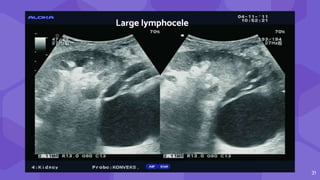

LYMPHOCELES SEROMAS

● Usg : anechoic/ hypo fluid collections

● CT round, hypoattenuating collections of clear fluid

● MRI visualizes lymphoceles, seromas and urinomas very similarly

31

Large lymphocele

30 LYMPHOCELES SEROMAS ⬢ Sxdisruption of lymphatics ⬢ Late post transplant( months) ⬢ Tend to grow ⬢ Chylous & triglycerides ⬢ Clear fluid ● Usg : anechoic/ hypo fluid collections ● CT round, hypoattenuating collections of clear fluid ● MRI visualizes lymphoceles, seromas and urinomas very similarly

• #31 Lymphoceles result from surgical disruption of lymphatics, they usually occur in the late posttransplant period, a month or several months after the surgery. lymphocele is the most commonly encountered perinephric fluid collection, typically occurring 2 weeks to 6 months after surgery, The key to differentiation of lymphoceles from seromas is that lymphoceles occur later and tend to grow. Seromas are composed of clear liquid, while lymphoceles have chylous content and contain triglycerides. In both cases, ultrasound shows an anechogenic cystic structure (Fig. 10), rarely containing internal debris or septations (15). CT displays round, hypoattenuating collections of clear liquid, without postcontrast imbibition. MRI visualizes lymphoceles, seromas and urinomas very similarly, on T1 low signal intensity collections and on T2 measured time as high signal intensity collections.

• #32  Large lymphoceles located dorsally of the renal transplant, 45 days after transplantation.